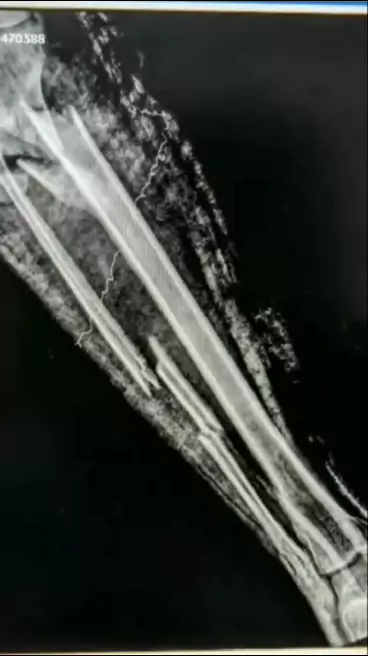

Depois dizem que Radiologia é só apertar botão🙂 #radiologia #anatomia #radiologiamedica